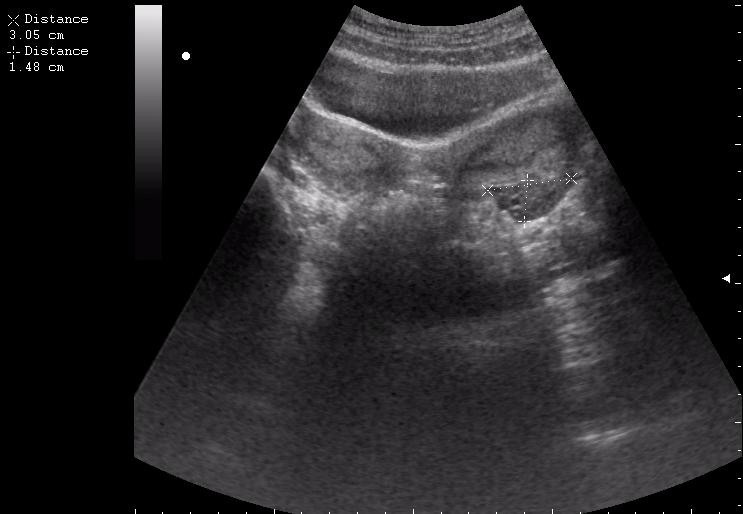

Матка и придатки. Молочные железы.

Супервумен